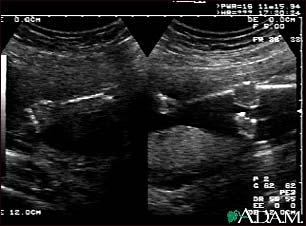

Ultrasound, normal fetus - arms and legs

This is a normal fetal ultrasound performed at 19 weeks gestation. This is the type of spilt-screen display you might see during an ultrasound, or if the technician prints a copy of the ultrasound for you. This ultrasound shows both the left arm (seen in the left side of the display), and the lower extremities (seen in the right side of the display). The white areas of the arm or legs is developing bone.